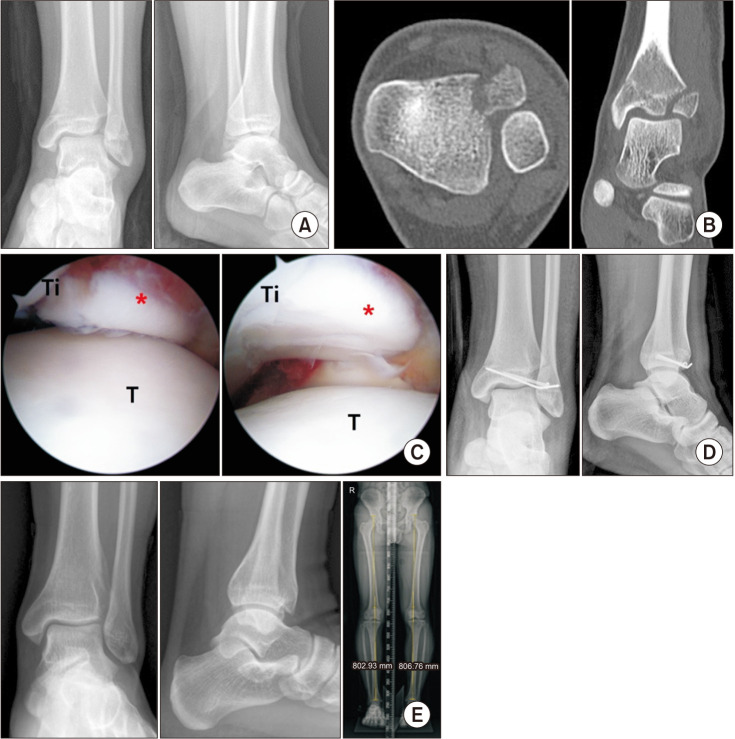

背景:本研究旨在比较关节镜下复位经皮内固定与切开复位内固定治疗踝关节内骺骨折的临床效果。方法:我们对2016年至2021年间连续接受关节内骨骺踝关节手术的患者进行了回顾性研究。共纳入88例患者,分为2组:关节镜复位组(AS组)和常规切开复位组(OR组)。15名患者被分配到AS组,30名患者从OR组中选择,考虑到人口统计学、骨折形态和随访时间,采用2:1的倾向评分匹配。临床结果采用足踝预后评分(FAOS)进行评估,而影像学评估用于评估骨愈合和关节面一致性。我们还分析了并发症,如感染、骨不连、成角、腿长差异和创伤后骨关节炎。结果:组间随访时间统计学差异有统计学意义(p = 0.04);然而,成功的倾向评分匹配消除了组间人口统计学和骨折配置变量的差异(均p < 0.05)。创伤的病因在其他变量上相似(p < 0.05)。两组术后FAOS均为良至优,两组间差异无统计学意义(p < 0.05)。两组均实现骨愈合,无骨不连,骨愈合时间和关节一致性无显著差异(p < 0.05)。虽然OR组并发症发生率高于AS组(3例vs. 0例),但差异无统计学意义(p = 0.083)。结论:关节镜复位和经皮内固定似乎是治疗关节内骨骺骨折的有效、微创选择,其结果与切开复位相当,并发症发生率低。

Methods: We conducted a retrospective review of consecutive patients who underwent intra-articular epiphyseal ankle surgery between 2016 and 2021. A total of 88 patients were included and divided into 2 groups: the arthroscopic reduction group (AS group) and the conventional open reduction group (OR group). Fifteen patients were allocated to the AS group, and 30 were selected from the OR group using propensity score matching in a 1 : 2 ratio, considering demographics, fracture configuration, and follow-up period. The clinical outcomes were assessed using the Foot and Ankle Outcome Score (FAOS), while radiological evaluations were used to assess bone union and the congruence of the articular surface. We also analyzed complications such as infection, nonunion, angulation, leg length discrepancy, and posttraumatic osteoarthritis.

Results: There was a significant difference in follow-up periods between the groups in terms of demographics (p = 0.04); however, successful propensity score matching eliminated any differences in demographic and fracture configuration variables between the groups (all p > 0.05). The etiology of trauma was similar across other variables (p > 0.05). Postoperative FAOS ranged from good to excellent in both groups, with no significant differences between them (all p > 0.05). Both groups achieved bone union without nonunion, with no significant differences in bone union time or joint congruency (all p > 0.05). Although there were more complications in the OR group than in the AS group (3 vs. 0 cases), this difference was not statistically significant (p = 0.083).

Conclusions: Arthroscopic reduction and percutaneous fixation appear to be effective, minimally invasive options for the treatment of intra-articular epiphyseal ankle fractures, offering outcomes comparable to open reduction with a low rate of complications.